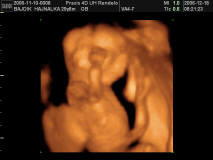

Melcsinek ez az arányszám valóban jó. Ehhez nézik ám az életkort is, és az minél magasabb, annál rosszabb arányszám jön ki. A határérték azt hiszem 1:150, és ez konkrétan azt jelenti, hogy a baba 1%(!) valószínűséggel Down kóros. Ha ettől rosszabb az arányszám, csak akkor javasolják az amniot. Ennek a markernek a megbízhatósága 95%, az amnióé 97 v. 98%! Tehát az se 100%!

Szerintem ne ess pánikba, a 2,9mm nem jelent egyértelműen bajt! Tényleg! Szerintem neked az a 18. heti vizsgálat egy genetikai uh lesz. Én is megyek ilyenre hétfőn. Nekem azt mondták, hogy ez az uh azért olyan fontos (egyébként úgy tudom kötelező is ), mert itt nagyon alaposan meg tudják nézni a babát: a szívkamráitól kezdve az agyáig mindent!